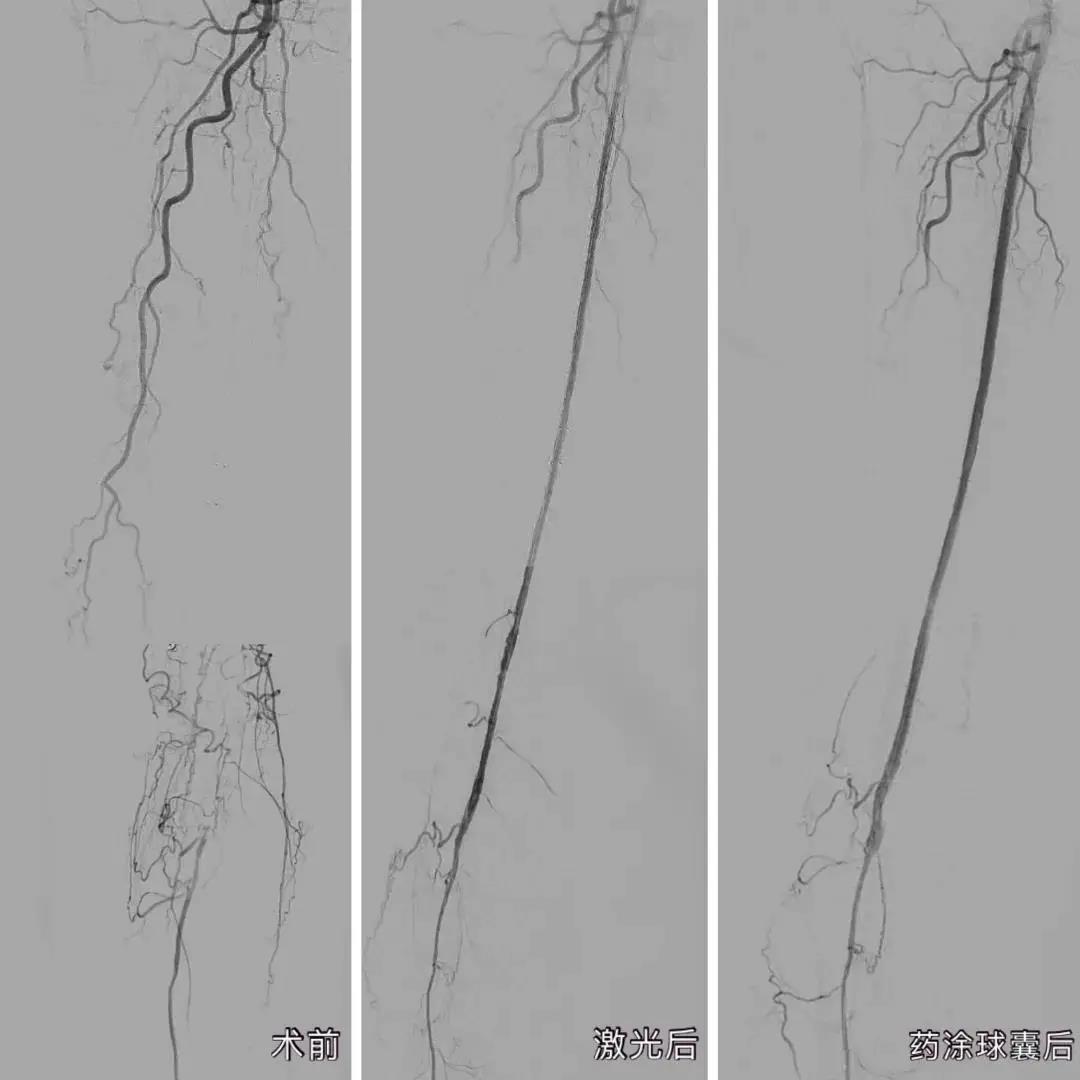

近日,厦心血管外科利用“准分子激光消蚀技术”联合“药物涂层球囊”技术,成功让这名双下肢动脉硬化闭塞患者的血管恢复通畅。

经过完善的术前准备,庄晖主任率团队在患者大腿的动脉,穿刺了一个仅绿豆般大小的口子,将激光导管从小洞中引入到堵塞的血管中,用准分子激光进行开通。仅是激光消蚀减容还不够,医生又使用了药物涂层球囊,通过球囊扩张,将一种防止内膜增生的药物涂到血管内壁上,从而达到长期抑制血管再狭窄的效果,“通俗来说,就是起到防止血管内再长‘水垢’的作用。”

手术过程顺利,术后造影结果下肢动脉病变部位全程血流通畅。经过厦心护理团队的细心看护,郑奶奶手术后第二天就可以下床活动,术后不到一周便解除了疼痛,完全正常行走。